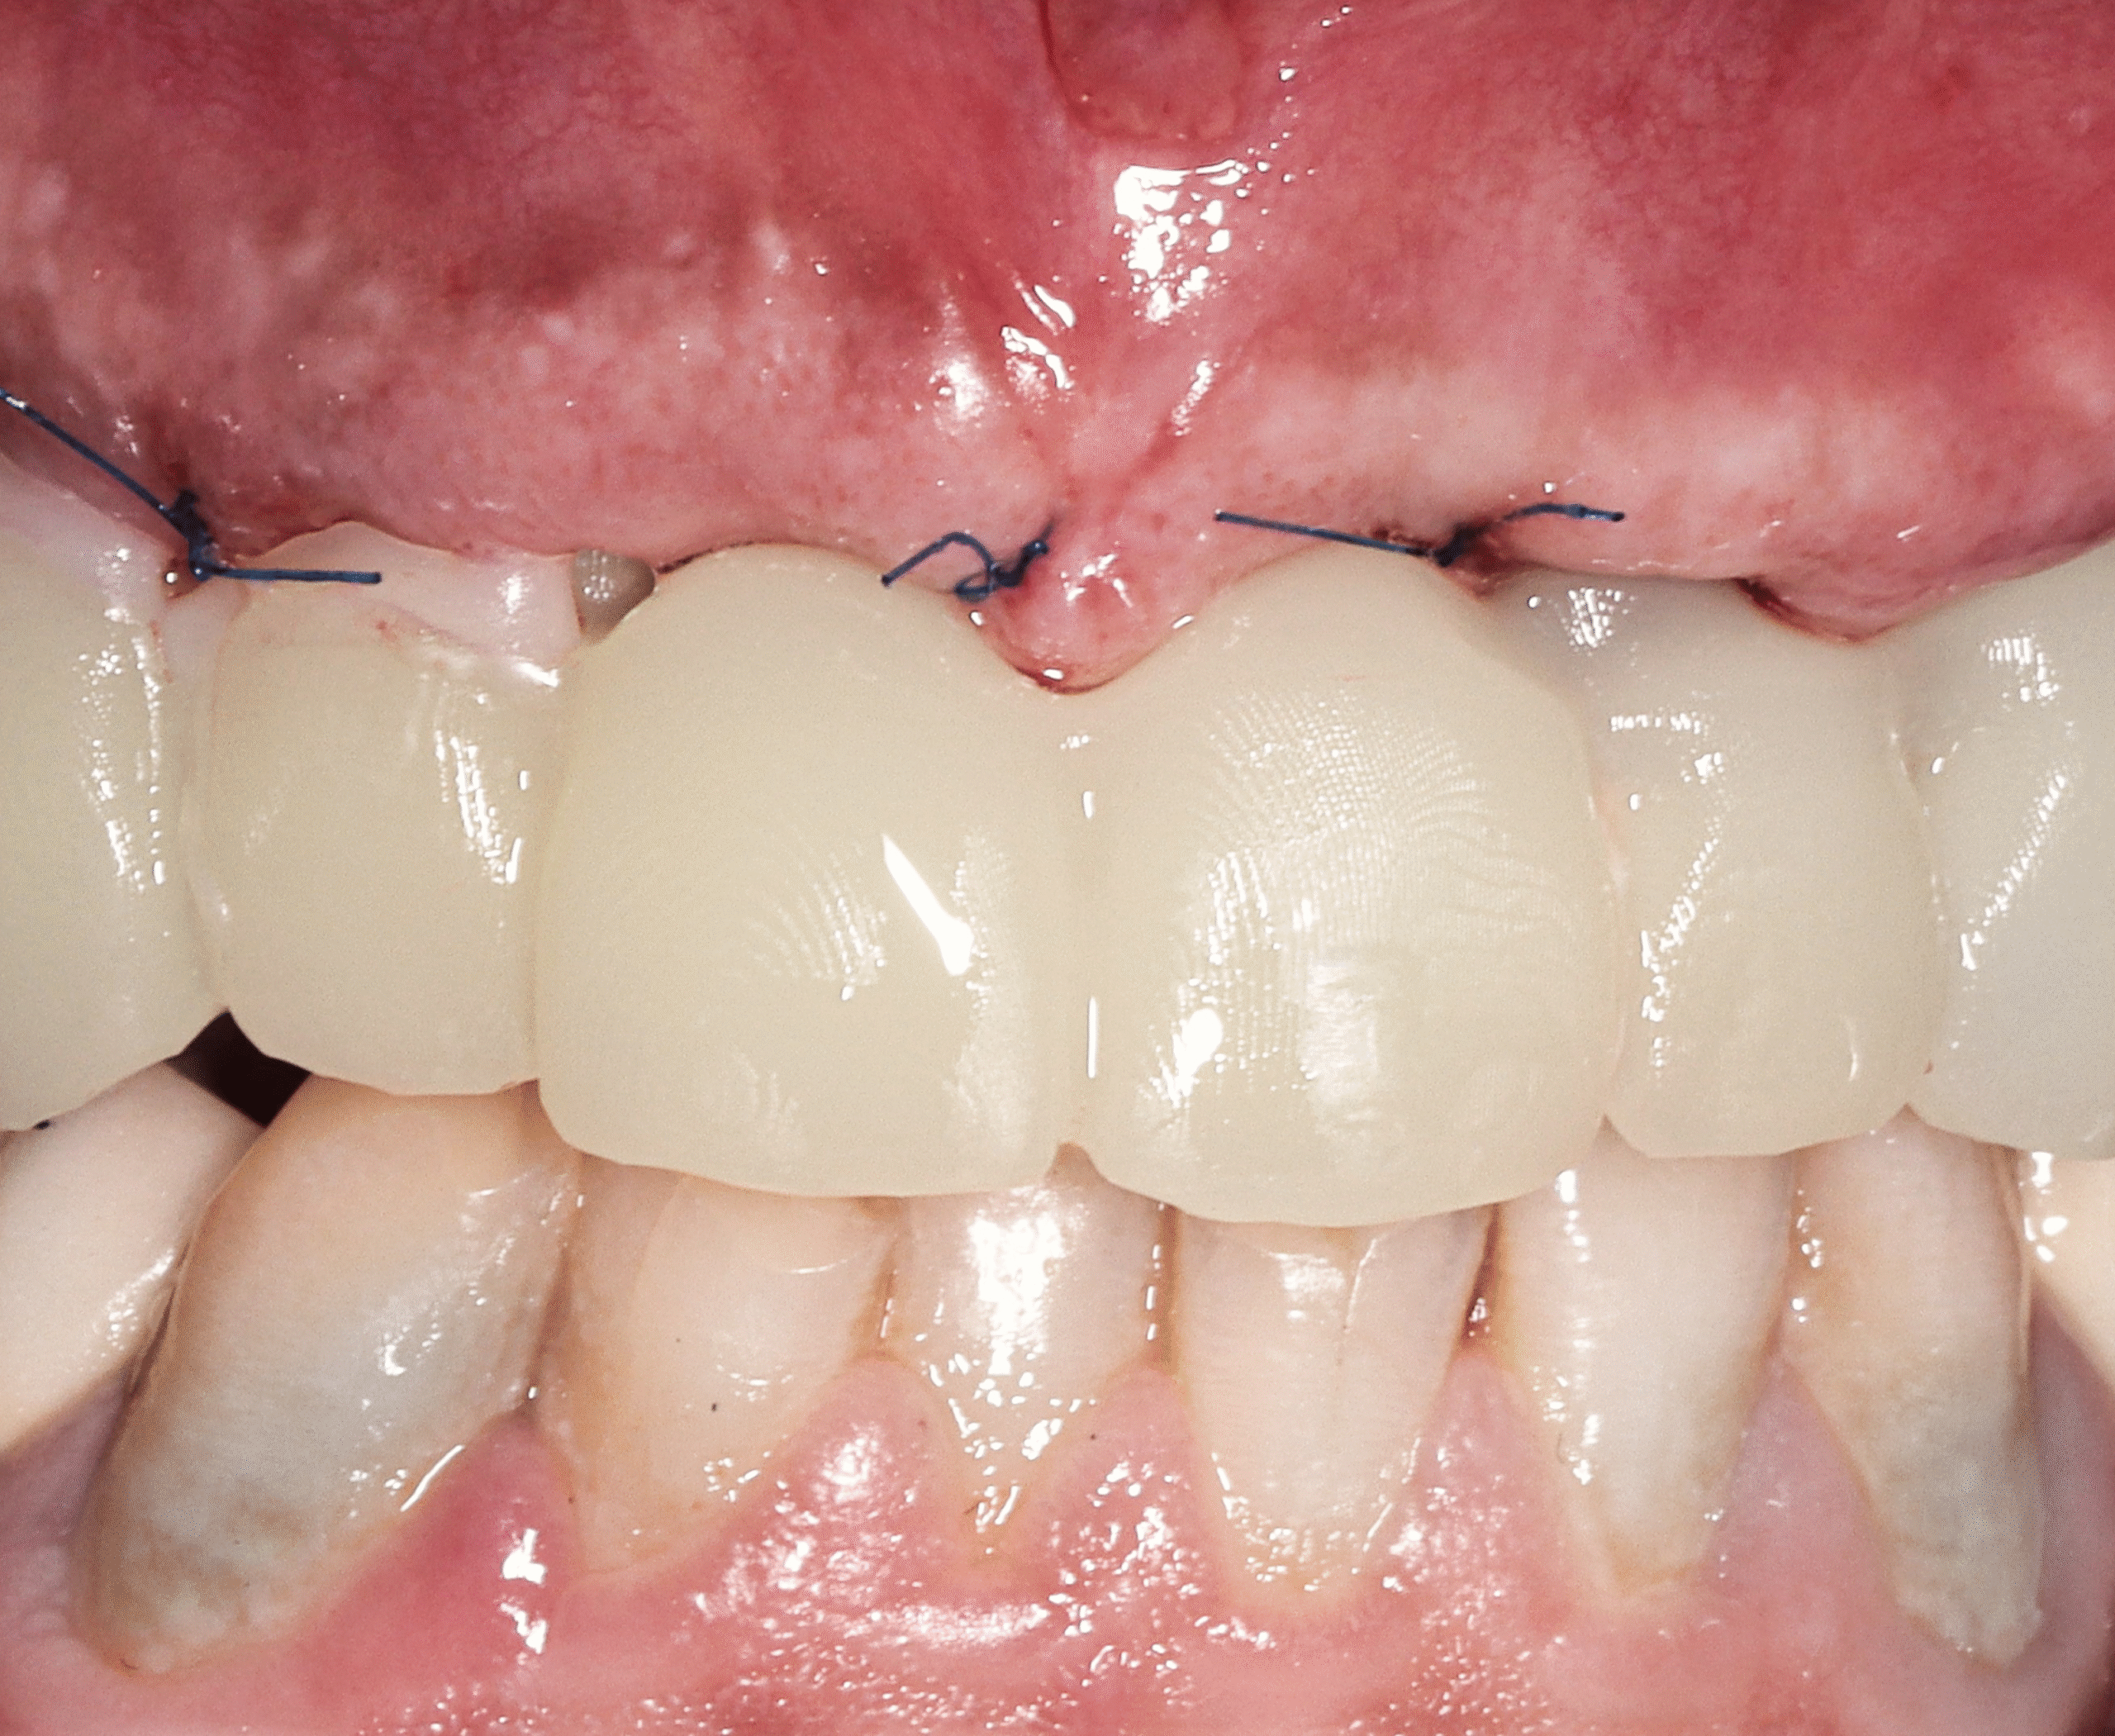

After

Step 5 — Final Prosthesis After Healing

- Fabrication of a durable, esthetic full-arch prosthesis

- Customized design to achieve natural appearance and optimal long-term function

Outcome

Jonathan’s transformation was both functional and aesthetic.

With his new full-arch restorations, he regained:

- A natural, youthful smile

- Full chewing ability and improved speech

- Proper facial support and proportion

- Renewed self-confidence and comfort in social interactions

This case demonstrates the effectiveness of the All-on-Four approach for younger patients experiencing advanced tooth loss. Through precise implant placement and immediate restoration, Jonathan achieved a stable, natural-looking, and life-changing result.